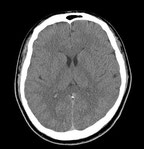

CT検査

CTとは Computed Tomographyの略で、日本語ではコンピューター断層撮影と呼びます。人体を中心としてX線を照射する機械を回転させ、身体の断層像を撮影することが出来ます。最近の装置ではコンピューター処理によって横断面(輪切り)だけではなく、様々な方向の断層像を作成することができ、立体的な3D画像を作成することもできます。

昨今では、マルチスライス(多列化)という機器の進歩により、広範囲の撮影を1回の息止めで行うことが可能となり、非常に高精細な画像を得ることができるようになりました。息を止める時間も短く、検査時間も短時間で済むので、従来のCTに比べ患者様の負担も大幅に軽減しています。

*病気を見逃さないためにはCT検査で撮影した画像の読影がより重要となります。当院では正確な診断を行うために、専門的な修練を積んだ日本医学放射線学会の診断専門医として熊本大学医学部付属病院 画像診断・治療科医師による読影を行っています。

16列マルチスライスCT装置

ECLOS16(日立メディコ製)

(頭部) |

(胸部) |

(腹部) |

*病気を見逃さないためにはCT検査で撮影した画像の読影がより重要となります。当院では正確な診断を行うために、専門的な修練を積んだ日本医学放射線学会の診断専門医として熊本大学医学部付属病院 画像診断・治療科医師による読影を行っています。